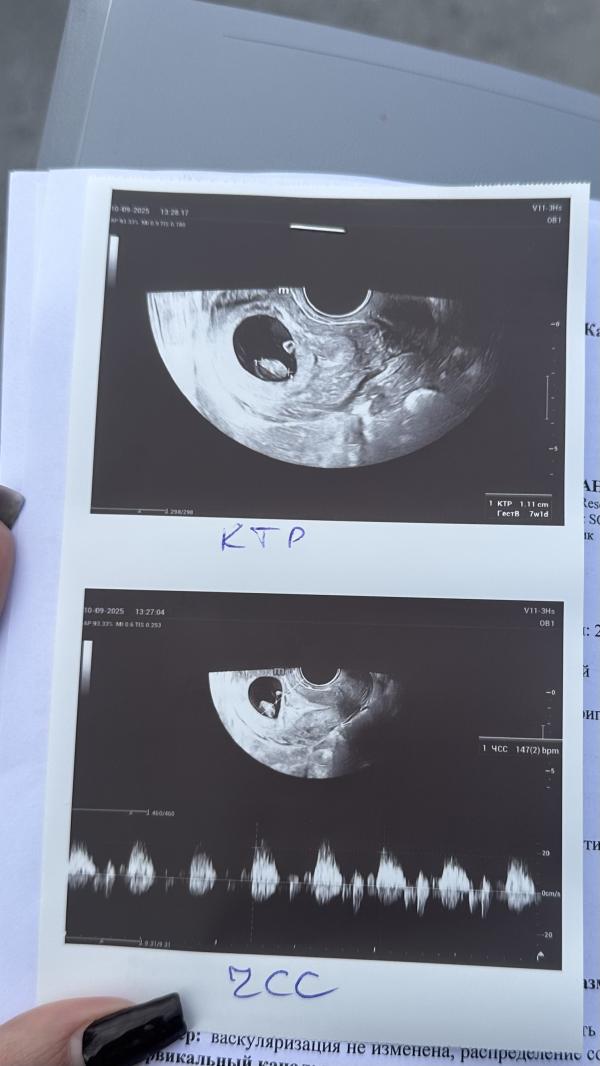

УЗИ показало сердцебиение эмбриона: история радости и переживаний

Сходила на узи, включили сердечко опять. Эмбриончик подрос, все отлично💗 зря вчера не наслаждалась прекрасным днем и самочувствием. Ну теперь буду знать))